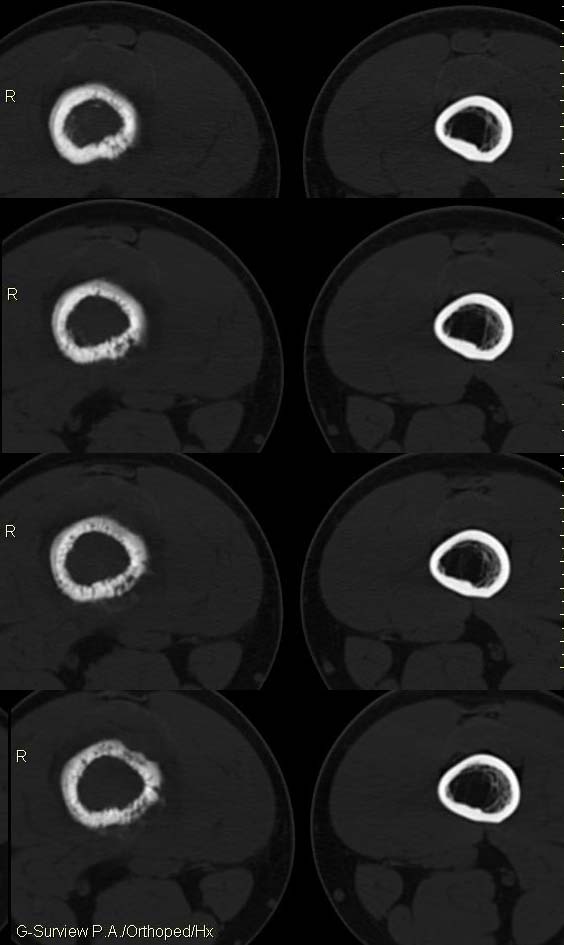

20岁,男,右股骨下端疼痛一个月,无发热,白细胞正常,皮肤不红,肿胀,触痛。

右股骨下端很长范围内的髓腔扩大,骨小梁破坏消失,皮质亦呈融骨性破坏,周围脂肪层次紊乱,肌肉受累及密度减低。考虑为:恶性骨肿瘤。请专家们分析骨肉瘤及尤文氏肉瘤的ct征象。

6.ct及mri:能较好地判断肿瘤的范围及侵犯软组织的情况。mri可见瘤体处广泛性骨质破坏,呈软组织肿块影;在t1加权像上呈均匀的长t1信号;在t2加权像上呈很长t2高信号。在ct上显示为源于骨组织的软组织肿块,骨质广泛破坏。

长骨ct见的较少,该病例股骨下端表现为边缘模糊的溶骨性破坏,伴有费用性脱钙,髓腔密度增高,呈毛玻璃样改变,病变周围软组织肿胀,脂肪间隙模糊,无骨膜反应,应密切结合临床,考虑骨纤维肉瘤或慢性骨脓肿。期待结果。

此病例基本可定是恶性骨肿瘤:髓腔内长范围肿块、皮质不规则破坏、软块及软组织浸润、瘤骨及不规则骨膜反应等。可以肯定地除外炎性病变和骨纤。

结合临床还是将尤文氏肉瘤放在前面,骨肉瘤不排除。纤维肉瘤及恶纤组多见老年人,不放在首要诊断范围内。